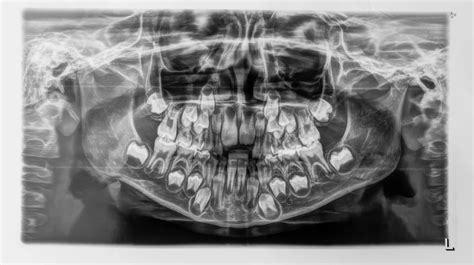

Las radiografías de un niño de 6 años, la primera vez que las ves, dan un poco de miedo, porque puedes ver los dientes de leche y todas las definitivas escondidas debajo. Cada vez que cae un diente de leche lo habitual es que erupcione un diente definitivo ese espacio. Por ello, cuando miramos una radiografía de un niño menor de 13 años podemos ver una tanda de dientes y debajo otra hilera de dientes.

Al caer los dientes de leche lo que observamos son las coronas o parte visible en boca del diente. Sobre los 6 años de edad, el niño experimenta la caída del primer diente anterior y la salida del primer diente definitivo. Generalmente el primer diente en caer y aparecer suele ser el incisivo central inferior.

Los dientes de leche son las 20 piezas dentales primarias que aparecen durante los tres primeros años de vida de un bebé. Empiezan a desprenderse alrededor de los 6 años y su proceso fisiológico no termina hasta los 12 aproximadamente. Esto se da gracias a una absorción de las raíces que sostienen los dientes, permitiendo su inestabilidad y caída.

La función desempeñada por esta dentadura primeriza es de vital importancia, ya que mantiene el espacio adecuada en la mandíbula mientras se forman los dientes definitivos por debajo de las encías.